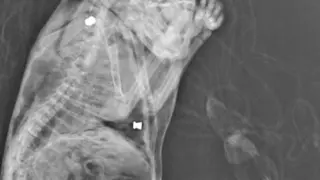

Ayuntamiento de Piedrahíta de Castro (2)

photo_camera Ayuntamiento de Piedrahíta de Castro (2)